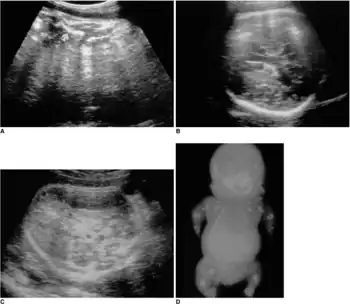

Achondrogenesis

Achondrogenesis is a number of disorders that are the most severe form of congenital chondrodysplasia (malformation of bones and cartilage). These conditions are characterized by a small body, short limbs, and other skeletal abnormalities. As a result of their serious health problems, infants with achondrogenesis are usually born prematurely, are stillborn, or die shortly after birth from respiratory failure. Some infants, however, have lived for a while with intensive medical support.

Researchers have described at least three forms of achondrogenesis, designated as Achondrogenesis type 1A, achondrogenesis type 1B and achondrogenesis type 2. These types are distinguished by their signs and symptoms, inheritance pattern, and genetic cause. Other types of achondrogenesis may exist, but they have not been characterized or their cause is unknown.